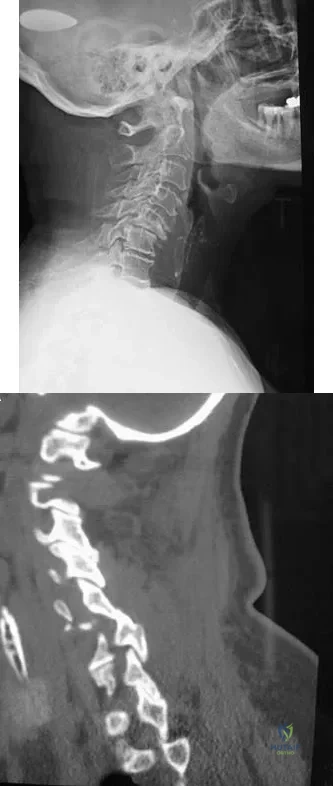

A 42-year-old woman reports that she has low back pain and had a transient loss of consciousness after falling off a horse. She denies having neck pain but notes that she was involved in a motor vehicle accident 2 years ago and had neck pain at that time. Examination reveals full range of motion of the neck and no localized tenderness. The neurologic examination is normal. A lateral radiograph of the cervical spine is obtained. Figures 41a and 41b show CT and MRI scans. What is the most likely diagnosis?

Explanation